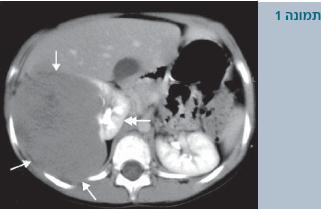

מלבד בדיקה גופנית שמצביעה במרבית המקרים על קיום של מסה בטנית, יש לבצע בדיקות מעבדה שיכללו: ספירת דם, כימיה מלאה (כולל תפקודי כליה), בדיקת שתן כללית (Urinalysis) ובדיקות דימות הכוללות על-קול בטן (Abdominal ultrasound), צילום חזה, וטומוגרפיה ממוחשבת (Computed tomography - CT) של הבטן (תמונה 1). במקומות מסוימים אף נהוג לבצע CT חזה או הדמיה בתהודה מגנטית (Magnetic resonance imaging - MRI).